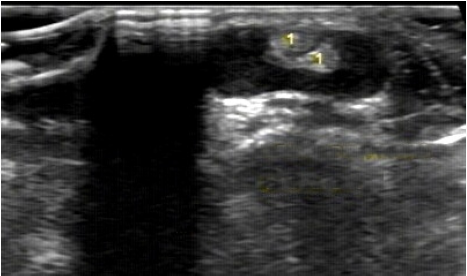

Na imagem, está representada uma tenossinovite do compartimento I (De Quervain). Os tendões deste compartimento são: